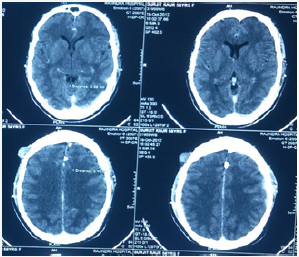

Figure 3: Radiograph skull showing no involvement of the skull bones.

A 58 year old female presented with pain in the left thigh and pelvis. She was originally radiographed (Figure 1 & 2) and was managed conservatively in the periphery. The radiographed of the skull showed no involvement of skull bones (Figure 3).Then the MRI of the femur and pelvis was done which reported it is as a cystic lesion and was advised extended curettage (Figure 4 & 5). No treatment was done. Two months after this the patient presented to us with greater pain and a pathological fracture left trochanteric region. The patient also had palpable subcutaneous masses in the head. We reviewed the MRI and did CECT pelvis and CECT head. CECT pelvis showed lytic expansile destruction of both the sacral ala with soft tissue masses extending into spinal canal causing compression of the cal sac in addition to the original lesion in the neck and trochanteric region with fracture (Figure 6). CECT head showed multiple lytic areas with formation of soft tissue masses in extra-calvirial and intra cranial locations (Figure 7). The brain parenchyma was normal. We did biopsy of the trochanteric region and nodule from scalp. Both the reports showed large tumour cells having round, irregular cleaved nuclei with 1-2 prominent nucleoli and moderate amount of cell cytoplasm with frequent mitotic figures (Figure 8). On immunohistochemistry were positive for LCA and CD-20 suggesting diffuse large B- cell lymphoma (Figure 9). The patient was then started on CHOP regime.